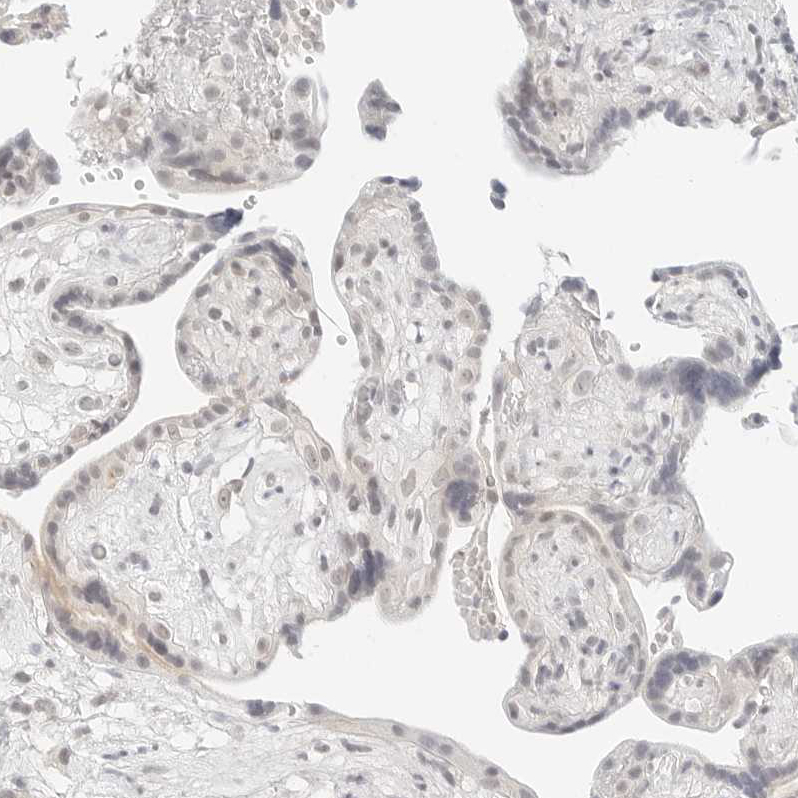

Immunohistochemical staining of human colon shows moderate cytoplasmic and membranous positivity in glandular cells.